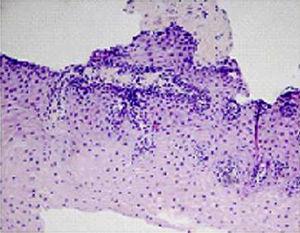

El paciente, tras varios intentos terapéuticos, se encontraba con una amplia dieta de exclusión e importante sintomatología (pirosis, disfagia, impactación de alimentos), aunque su desarrollo ponderoestatural era correcto. En ese momento se inicia tratamiento con budesonida viscosa por vía oral a dosis de 1g de budesonida/día durante 4 meses. Tras este periodo, el niño experimenta una mejoría importante de su sintomatología, con normalización macroscópica esofágica e infiltrados inflamatorios aislados en la histología (Figura 2).

Figura 2. Mucosa esofágica tras tratamiento con budesonida viscosa por vía oral. Aparece un mínimo infiltrado eosinófilo (< 5 eosinófilos/campo).